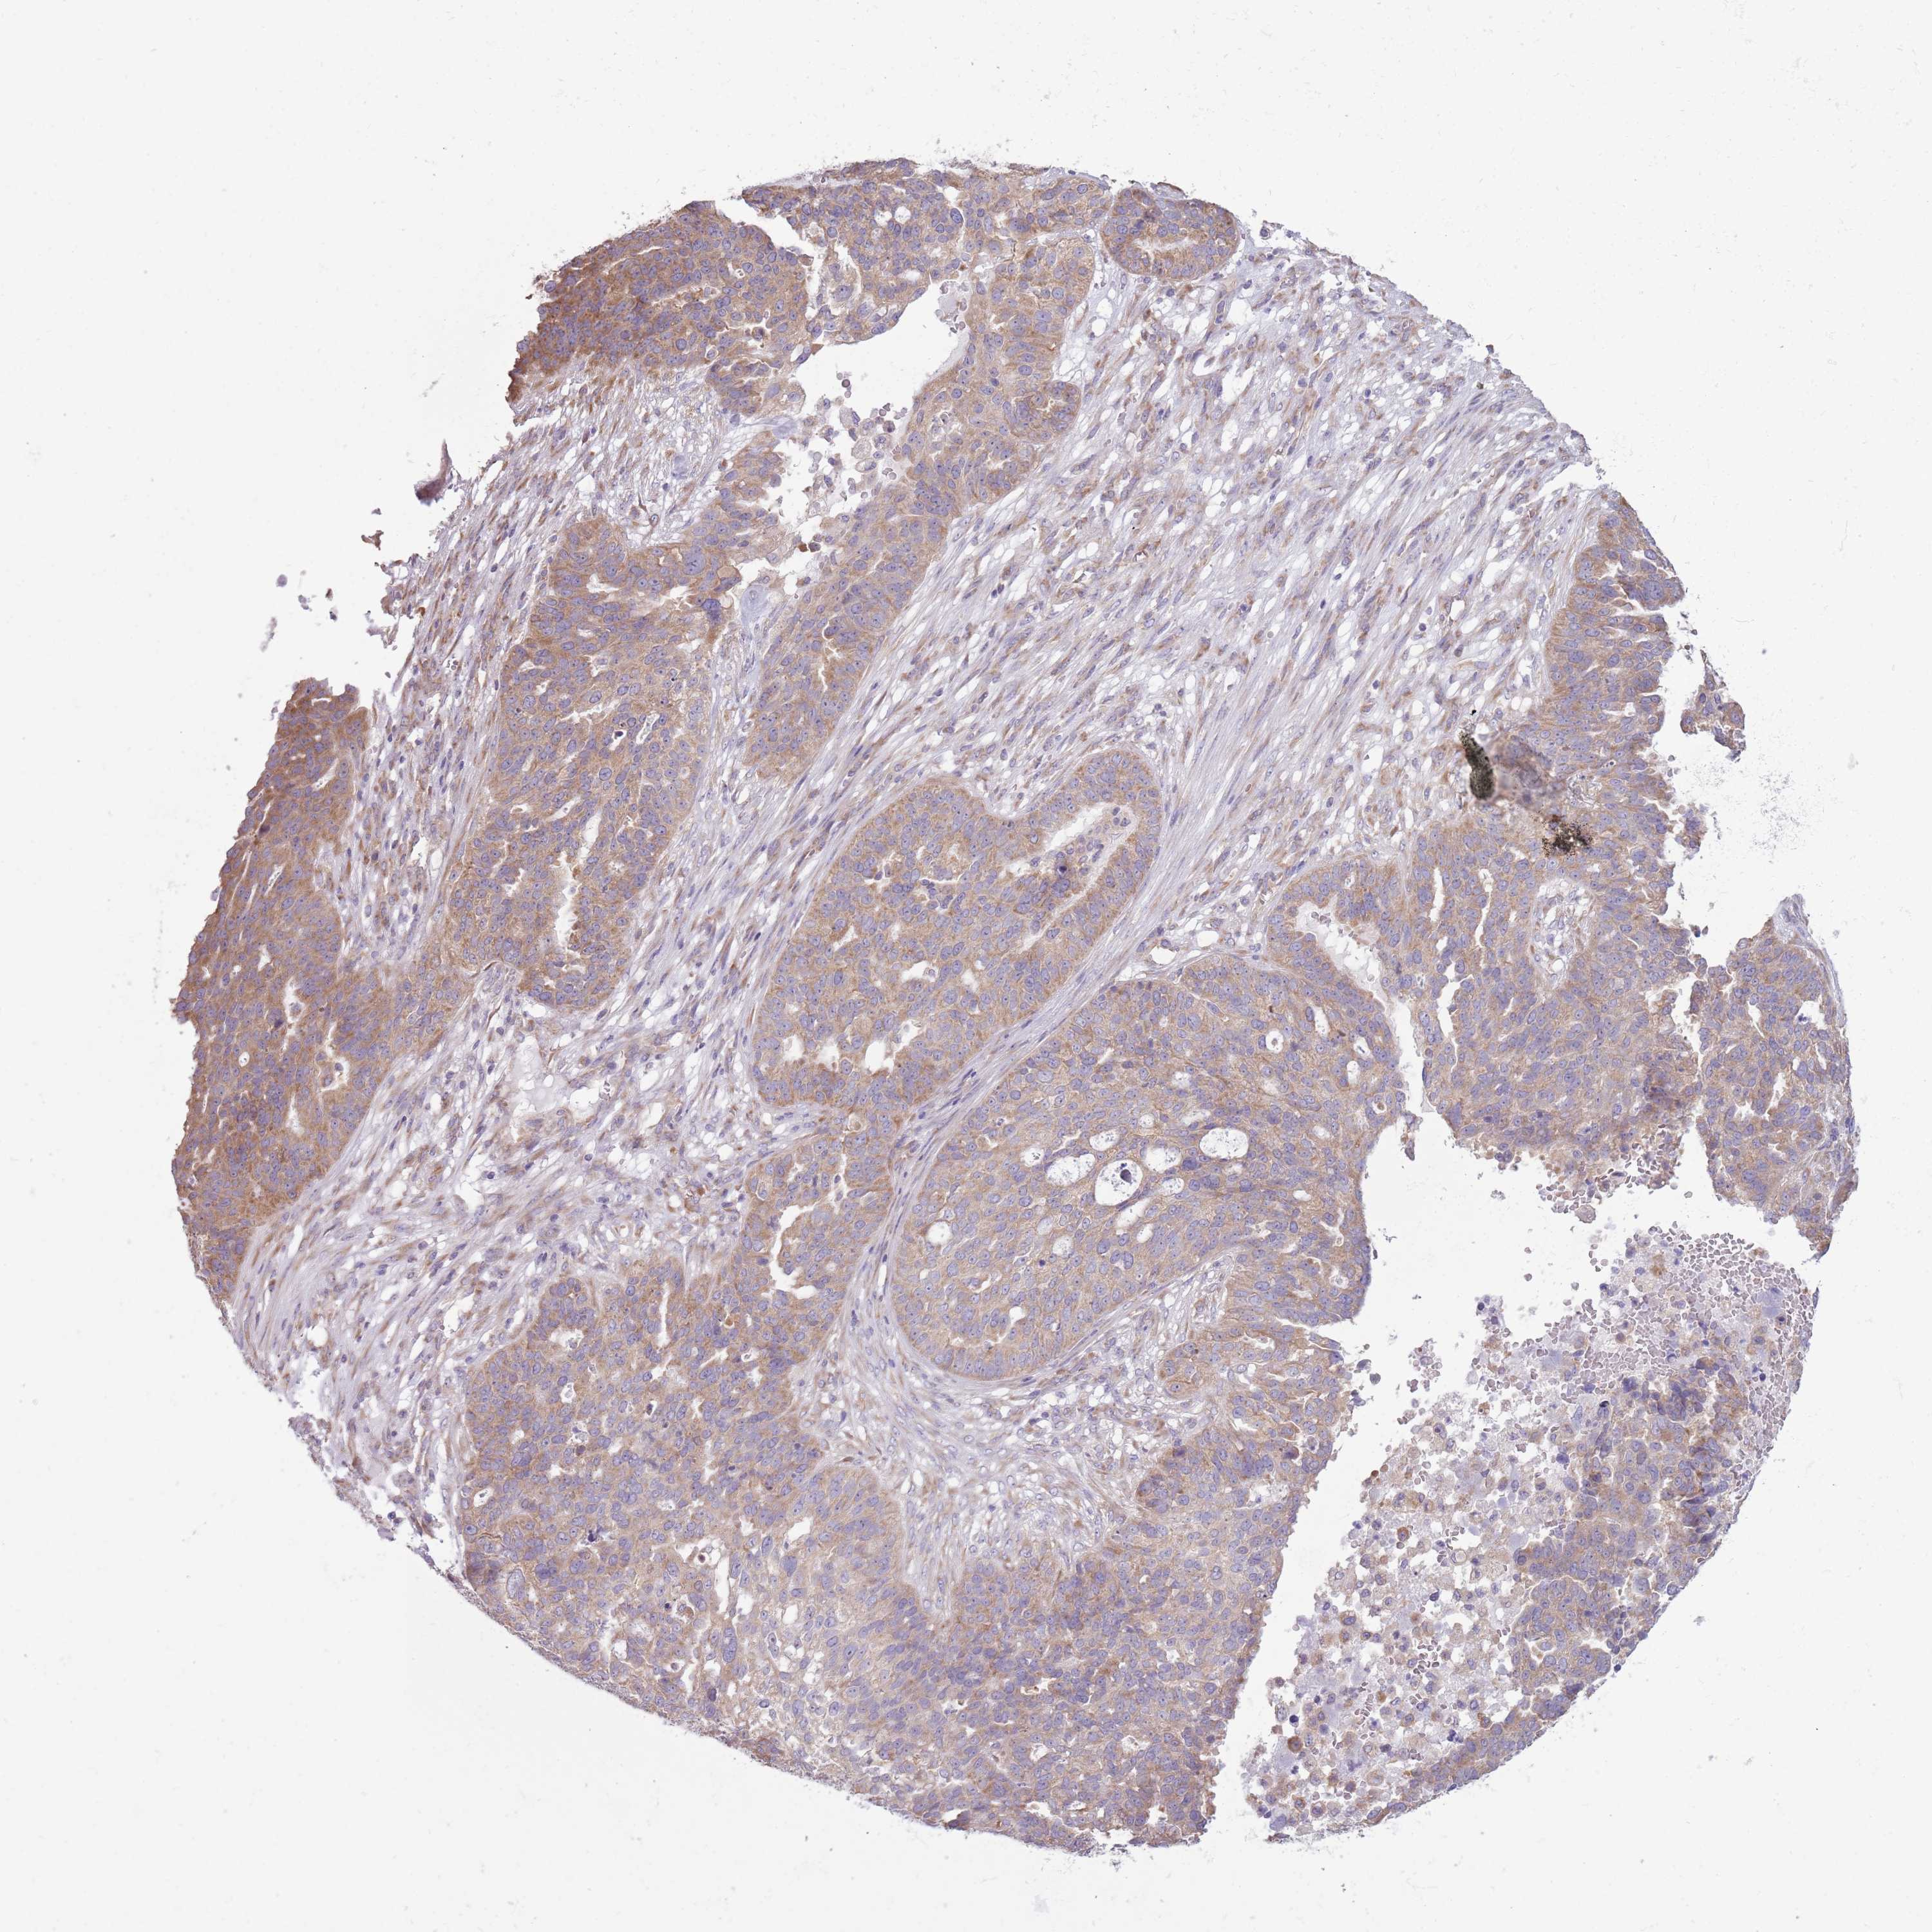

OVARIAN CANCER - Protein expressioni

A mouse-over function shows sample information and annotation data. Click on an image to view it in a full screen mode. Samples can be filtered based on level of antibody staining by selecting one or several of the following categories: high, medium, low and not detected. The assay and annotation is described here.

Note that samples used for immunohistochemistry by the Human Protein Atlas do not correspond to samples in the TCGA dataset.

Antibody stainingi

Antibody staining in the annotated cell types in the current human tissue is reported as not detected, low, medium, or high, based on conventional immunohistochemistry profiling in selected tissues. This score is based on the combination of the staining intensity and fraction of stained cells.

Each image is clickable and will lead to virtual microscopy that enables deeper exploration of all samples and also displays staining intensity scores, fraction scores and subcellular localization as well as patient and tissue information for each sample.

Antibody HPA043724

Antibody HPA046385

Cystadenocarcinoma, serous, NOS

Carcinoma, NOS

Cystadenocarcinoma, mucinous, NOS

Carcinoma, endometroid